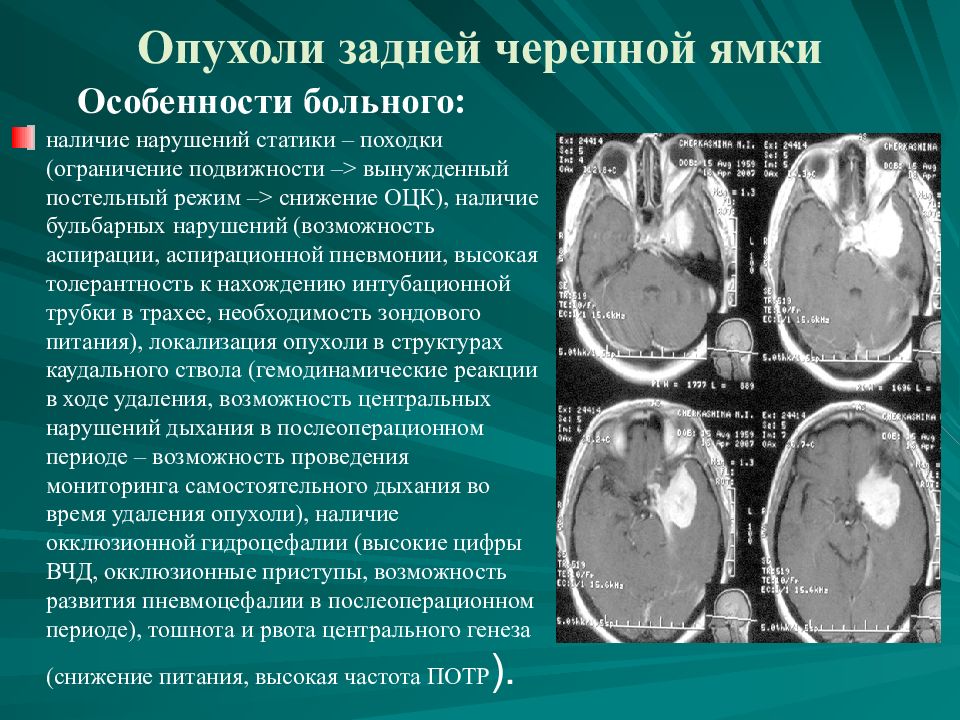

Кт при опухоли надпочечников. Кортикостерома надпочечника кт. МСКТ объемное образование надпочечника. Кт мрт аденома надпочечника. Опухоли задней черепной ямки. Объемное образование задней черепной ямки. Опухоли задней черепной ямки клиника.

Опухоли задней черепной ямки. Объемное образование задней черепной ямки. Опухоли задней черепной ямки клиника. Канцер молочной железы. Онкология грудной железы. Онкологические заболевания груди. Опухоль молочной железы.